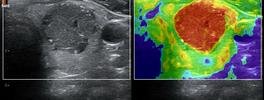

• High End SHEAR WAVE ELASTOGRAPHY For LIVER FIBROSIS/THYROID MALIGNANCY/BREAST CANCER